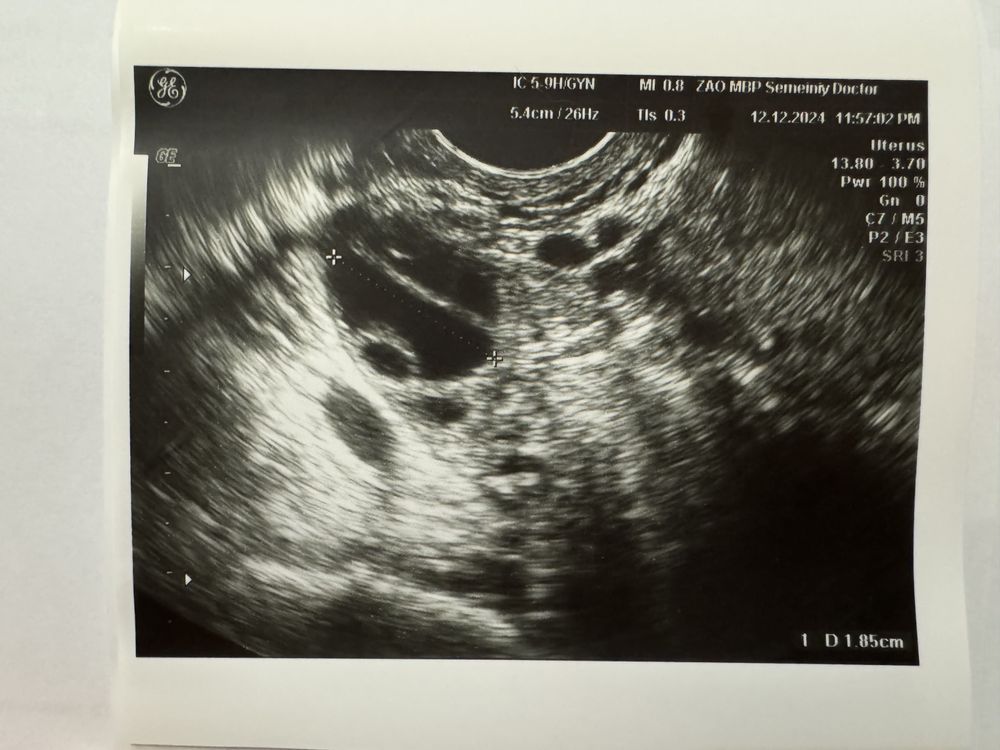

Изображение Изображение